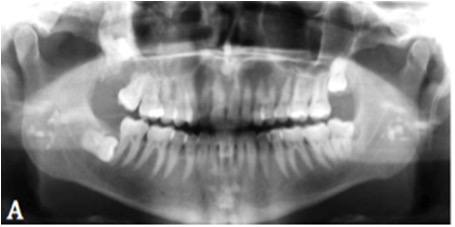

3. What condition can be seen in the following X ray?